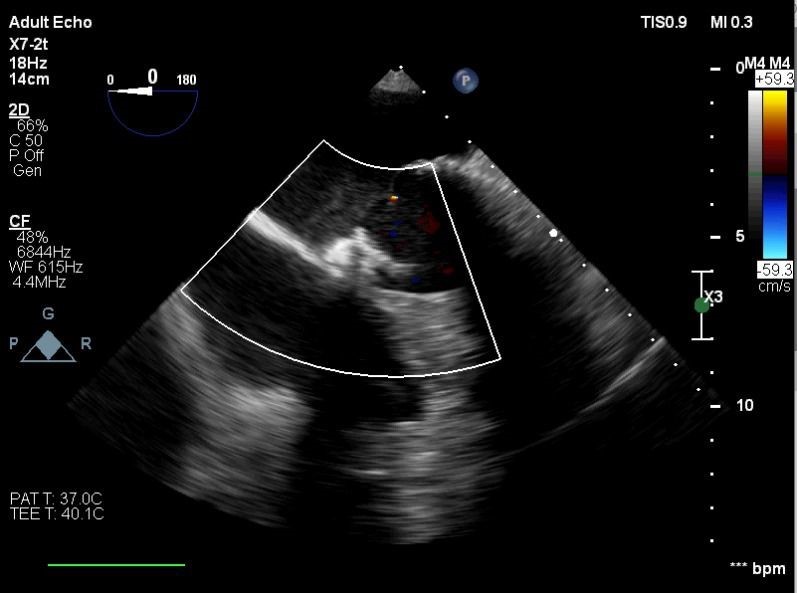

Balıkesir’de ilk nitelikli işlemlerin bir yenisi de Kardiyoloji Anabilim Dalı bünyesinde girişimsel kardiyoloji ile gerçekleştirilen paravalvüler kaçak kapatılması işlemi oldu. İşlem sırasında hastanın kalbi durdurulmadan ve göğüs kafesi kesilmeden, kasığından girilerek yapay kalp kapağındaki kaçak ameliyatsız kapatıldı.

Yapılan işlemi gerçekleştiren ekipte yer alan Prof. Dr. Halil Kısacık, Doç. Dr. Eyüp Avcı, Doç. Dr. Tarık Yıldırım ve Doç. Dr. Özgen Şafak konu hakkında açıklamalarda bulundu. Daha önce kalp kapakçığı değişim ameliyatı olan hastada takılan kapağın kenarından ayrılmasıyla kan kaçağı (paravalvuler leak) meydana geldiğini belirten öğretim üyeleri, Kardiyoloji Anabilim Dalına başvuran hastaya, Türkiye’de sayılı kalp merkezinde yapılan ve önemli düzeyde cerrahi deneyim gerektiren paravalvüler kaçak kapatılması işlemi uygulandığını dile getirdi. İşlemin sadece girişimsel kardiyologlar tarafından yapıldığının altını çizen öğretim üyeleri, işlem sırasında hastanın kalbi durdurulmadan ve göğüs kafesi kesilmeden, kasığından girilerek yapay kalp kapağındaki kaçağın ameliyatsız kapatıldığını söyledi.